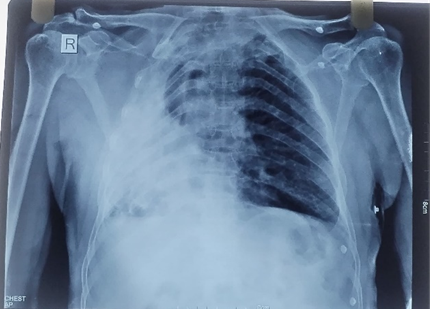

Coronary angiography demonstrated essentially normal coronary arteries. Chest radiographyconfirmed a destroyed right lungwith amild rightward mediastinal shift. ECGcontinued to show persistent ST elevations. Laboratory investigations showed: Hemoglobin: 8.8 g/dL (indicating mild anemia), White blood cell and platelet counts: within normal limits, Serum creatinine: 1.0 mg/dL (normal), Mild elevations in serum sodium and potassium levels.

Fig 03: Chest X-Ray